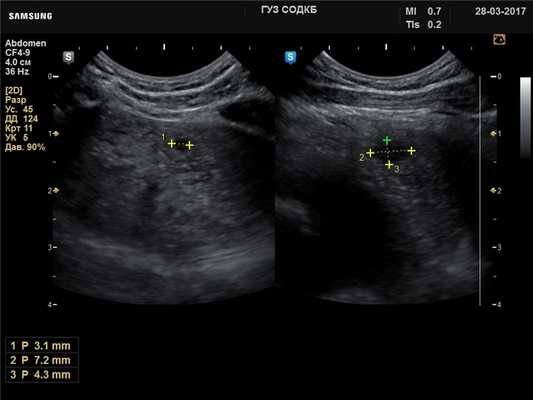

Тимус - киста, B-режим

[EN] Эхограмма №736: Киста тимуса (левой доли) у ребенка 2 лет. Микроконвексный датчик 4-9 МГц (неонатальный), двойной B-режим (слева - продольно, справа - поперечно).

Автор: Суханов С.А., Саратов.

Изображение получено с помощью УЗ сканера H60 (снят с производства).